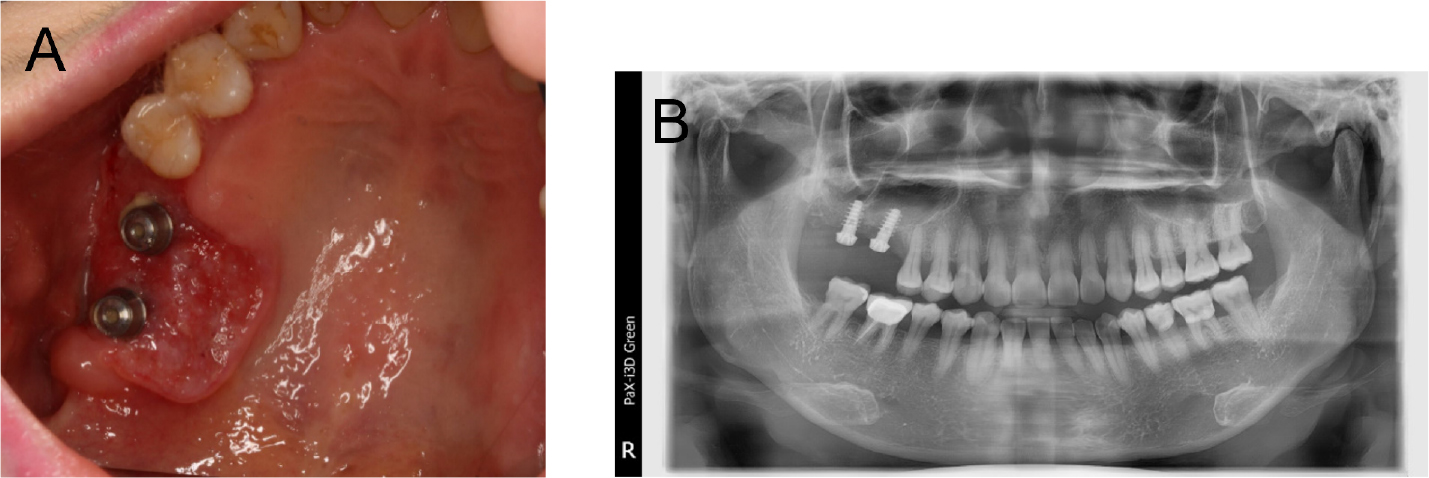

On December 10, 2019, a 56-year-old woman was referred to the Department of Oral and Maxillofacial Surgery at the Dental Hospital of Yonsei University with inflammatory symptoms in the right upper molar region. Examination revealed ulcerative lesions with indurations around previously placed dental implants (#16i and #17i). Discontinuity of the right maxillary sinus floor and alveolar bone loss around implant #16i and #17i were observed on the initial panoramic radiograph (Fig. 1). Incisional biopsy of the area revealed squamous cell carcinoma.